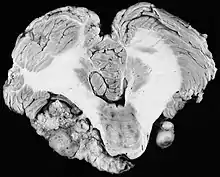

Schwannoma, Neuroma, Neurolemoma ou Neurilemoma é um tumor do sistema nervoso periférico originado nas células de Schwann. As células de Schwann são responsáveis pela criação de uma membrana isolante elétrica ao redor do axônio dos neurônios periféricos, a bainha de mielina, e também que atuam regenerando nervos. Geralmente o termo "Schwannoma" se refere a um tumor benigno e de crescimento lento. Os raros casos cancerosos devem ser chamados de Schwannoma maligno. [1]